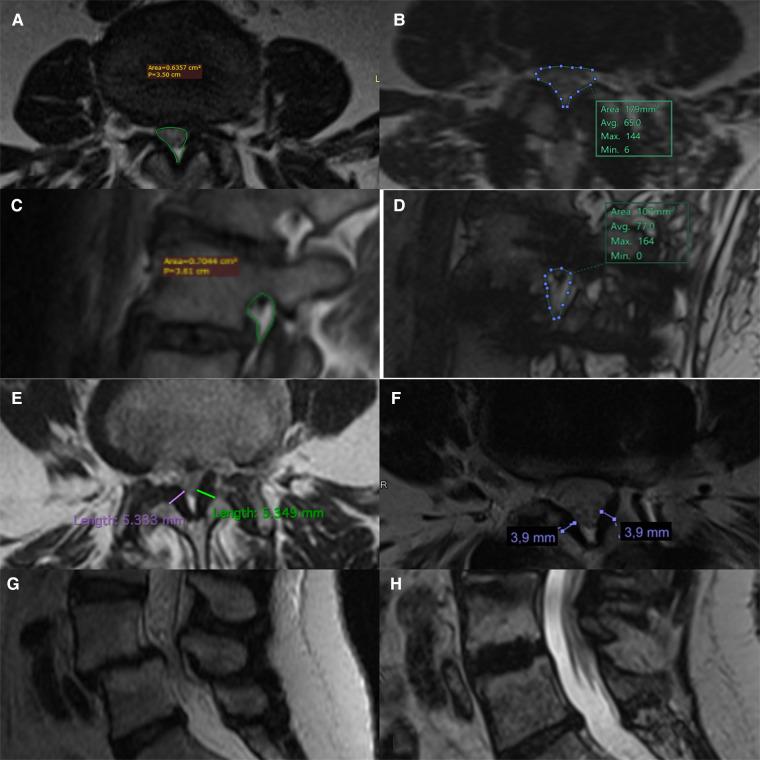

From 2016 to 2019, patients who underwent single- or double-level indirect decompression LLIF were consecutively reviewed. Radiological signs of indirect decompression were evaluated in preoperative and follow-up MRI studies and were subsequently correlated to clinical data, expressed as axial/radicular pain (VAS back/leg), index of disability (Oswestry Disability Index) and clinical severity of lumbar stenosis (Swiss Spinal Stenosis Questionnaire).

72 patients were enrolled. The mean follow-up was 24 months. Differences in vertebral canal area ( < 0.001), height of the foramina ( < 0.001), thickness of the yellow ligament ( = 0.001) and anterior height of the interbody space ( = 0.02) were observed. Older age ( = 0.042), presence of spondylolisthesis ( = 0.042), presence of intra-articular facet effusion ( = 0.003) and posterior height of the implanted cage ( = 0.020) positively affected the increase of the canal area. Change in root canal area ( < 0.001), height of the implanted cage ( = 0.020) and younger age ( = 0.035) were predictive factors of root pain relief, while increased vertebral canal area ( = 0.020) and height of the interbody fusion cage ( = 0.023) positively affected the severity of clinical stenosis.

共纳入72例患者。平均随访时间为24个月。观察到椎管面积(<0.001)、椎间孔高度(<0.001)、黄韧带厚度(=0.001)和椎间间隙前缘高度(=0.02)存在差异。年龄较大(=0.042)、存在椎体滑脱(=0.042)、关节内小关节积液(=0.003)和植入椎间融合器的后缘高度(=0.020)对椎管面积的增加有积极影响。根管面积变化(<0.001)、植入椎间融合器的高度(=0.020)和年龄较小(=0.035)是神经根性疼痛缓解的预测因素,而椎管面积增加(=0.020)和椎间融合器高度(=0.023)对临床狭窄严重程度有积极影响。